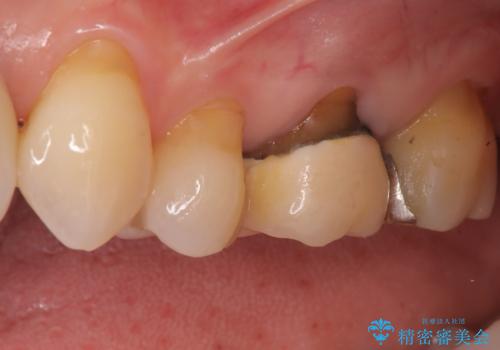

- 「以前治療した被せ物の色が気になる」「最近しみるようになった」との主訴で来院されました。診察の結果、古い被せ物の周囲に段差ができており、そこから虫歯が進行している状態でした。また、色も経年劣化により周囲の歯と調和が取れておらず、笑ったときに目立つとのお悩みもありました。

被せ物の下の虫歯を除去し、必要に応じて土台の補強を行ったうえで、見た目が自然で長期的な安定性もあるセラミッククラウンによる修復をご提案しました。見た目と機能の両方を改善するため、隣接する歯との色調や形態のバランスも考慮した治療計画を立てました。

まず古い被せ物を慎重に取り除き、中に広がっていた虫歯を丁寧に除去しました。歯質の状態を確認したうえで、必要な部分には土台(コア)を補強し、セラミッククラウンを装着する準備を整えました。

最終的な被せ物には、周囲の歯と自然になじむような色合い・透明感を持つセラミックを採用。形も元の歯に近づけ、違和感のない見た目と噛み心地を再現しました。